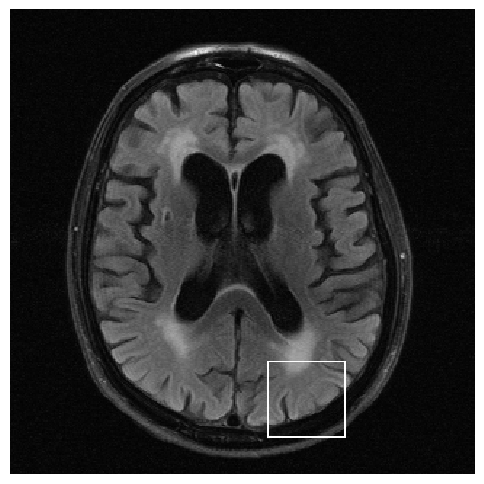

Figure 3: Examples of Reconstruction Results. Rows 1 and 3: The Ground truth (GT) fully sampled image, the reconstructed images obtained by the three models (1-3), NPB-REC, baseline, E2E-VarNet trained with Dropout, and the Std. map derived from our method for acceleration rates R=4𝑅4R=4, R=8𝑅8R=8, respectively. Rows 2 and 4: The corresponding annotated ROIS of the edema and resection cavity.

Fig. 3 presents examples of reconstruction results obtained by (1) our NPB-REC approach, (2) the baseline, and (3) Monte Carlo Dropout, for equispaced masks with two different acceleration rates R=4𝑅4R=4 and R=8𝑅8R=8. Table 1 presents the mean PSNR and SSIM metrics, calculated over the whole inference set, for the three models. our NPB-REC approach achieved significant improvements over the other methods in terms of PSNR and SSIM (Wilcoxon signed-rank test, pmuch-less-than\ll1e-4). The improvement in the reconstruction performance can be noted both quantitatively from the metrics especially for masks with acceleration rate R=8𝑅8R=8 and qualitatively via the images of annotations, where our results shows less smoothness than that obtained by Dropout.